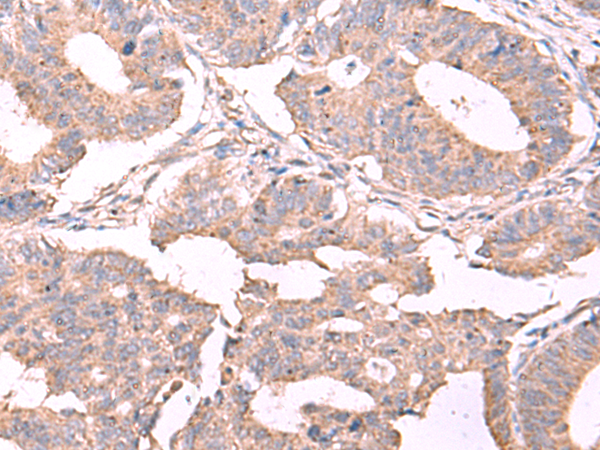

分类: 科研抗体货号: P08314别名: MLSTD1; SDR10E2应用: WB,IHC反应种属: Human, Mouse